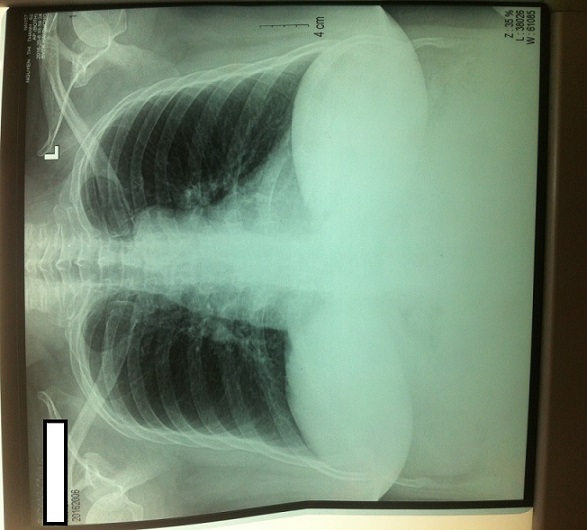

Phổi rì rào phế nang đều rõ hai bên, không có rale.

7. Chụp x quang xương bàn chân và lồng ngực: không thấy tổn thương.